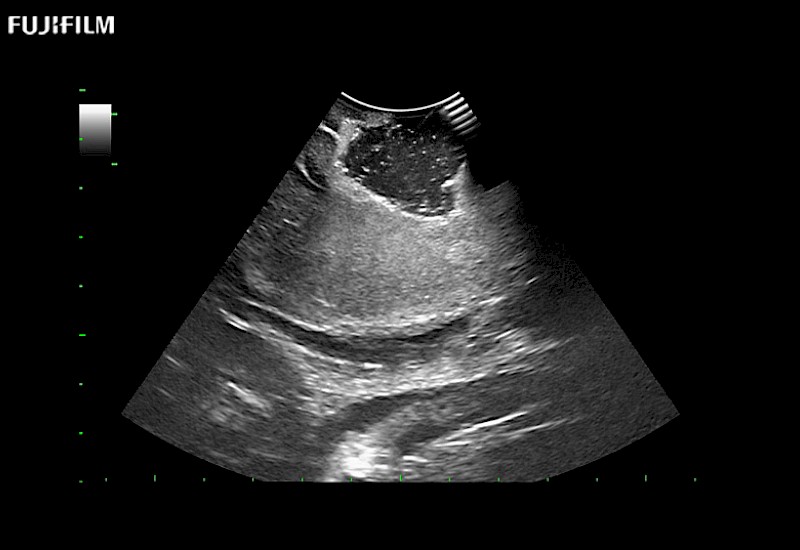

Fujifilm Healthcare understands that neurosurgeons demand excellence in their operating rooms — from their staff and the equipment they depend on. Fujifilm Healthcare's dedication to neurosurgery provides outstanding ultrasound technology, professional support, and the specialized tools necessary to best perform comprehensive real-time ultrasound imaging.

Dedicated Intraoperative Ultrasound

Solutions for Neurosurgeons

For precise neurosurgery ultrasound imaging, Fujifilm Healthcare offers premium level solutions that include:

Extraordinary high-resolution digital imaging

Exceptional transducers

for use during: Cranial guidance, Burr-Hole guidance, Spinal Cord guidance, Pituitary guidance, Micro-Surgery guidance

Our dedication to neurosurgery allows us to offer superior image quality, outstanding system reliability and intuitive use of cutting edge technology.